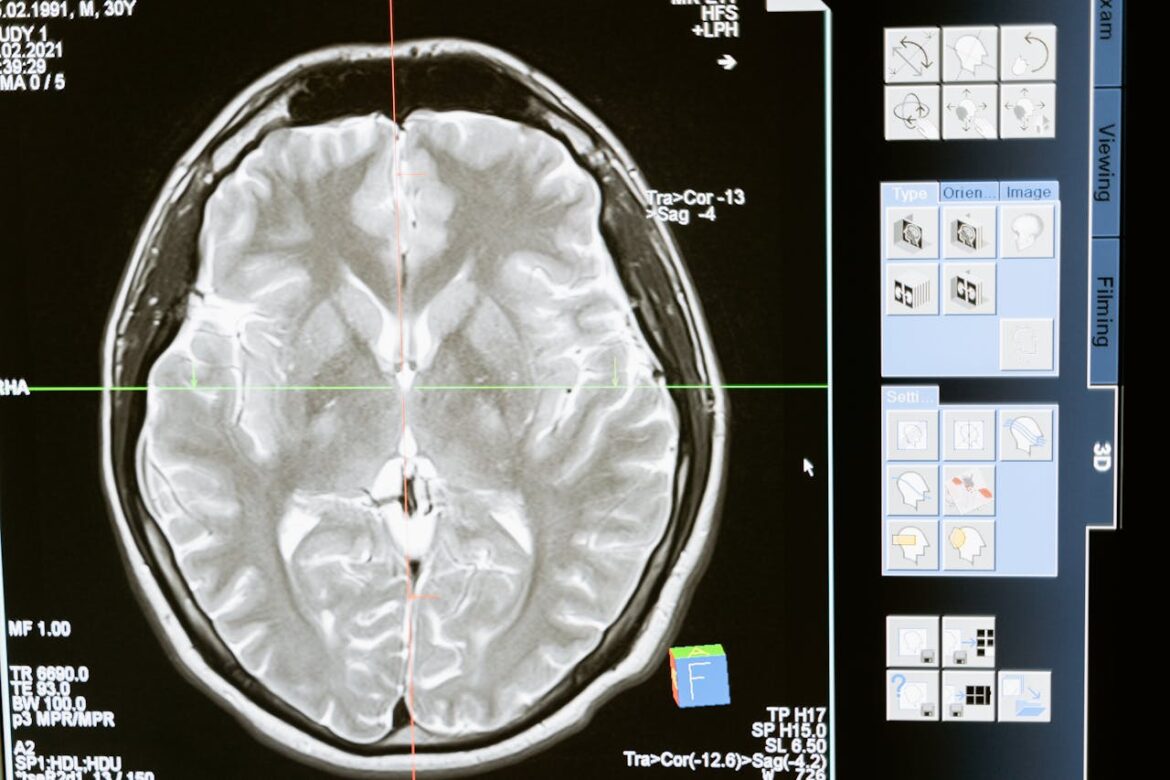

Chronic Traumatic Encephalopathy (CTE) is a progressive neurodegenerative disease that is primarily caused by repeated head injuries, such as concussions. It is characterized by the accumulation of an abnormal protein called tau, which forms clumps and gradually spreads throughout the brain, leading to the death of brain cells. People with CTE may experience a range of symptoms, including memory loss, confusion, impaired judgment, aggression, depression, anxiety, and progressive dementia.

Diagnosing CTE is challenging as it is often done posthumously through brain autopsies. This limitation makes it difficult to study and diagnose in living individuals. Nonetheless, ongoing research is focused on developing methods for early detection and intervention in an effort to improve outcomes for those at risk of developing the condition.